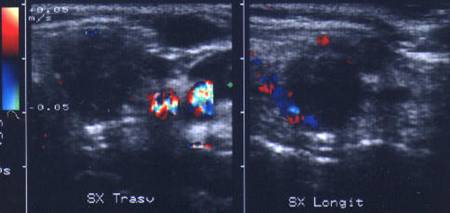

Apexul lobului drept, proiectie longitudinala si trasversala.

Femeie 58 ani. Maladia Graves in tratament cu

metimazol.

Nodul unic in apexul lobului drept, de 11x14x20mm (1,5 cc), hipoecogen, cu

contur difuz

Nu s-a efetuat citoaspiratie.

Aceeasi pacienta. La ecodoppler color - vascularizatie

periferica, avascular intralezional.

Ecopowerdoppler confirma absenta vascularizatiei interne.